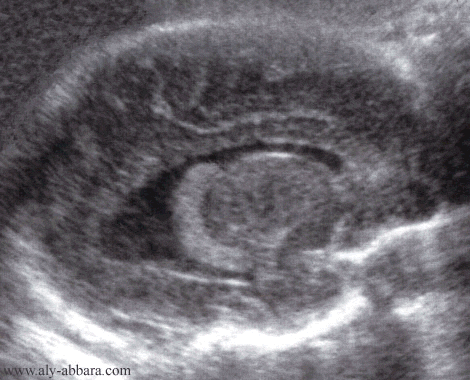

Coupe parasagittale du cerveau fœtal à 28 semaines d'aménorrhée

Mise en évidence du ventricule latéral et les organes anatomiques avoisinants